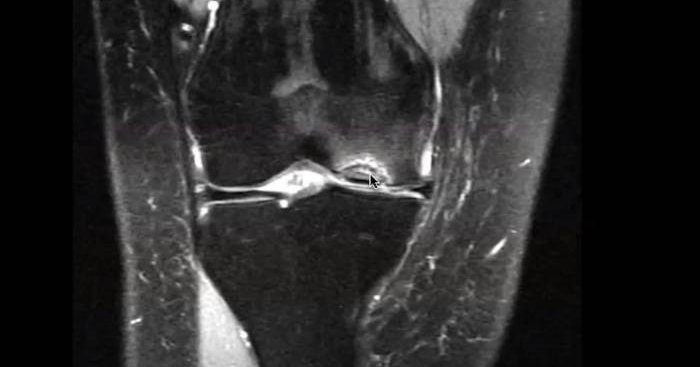

A medial #meniscustear may require surgery if it causes pain during twisting, turning, pivoting, or squatting...or if it’s a complex tear that risks further damage. Repairs can help prevent future arthritis in younger patients with healthy cartilage.

A medial meniscus tear is more common than a lateral meniscus tear, because it is firmly attached to the deep medial collateral ligament and the joint capsule.